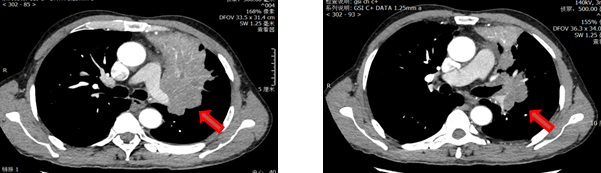

邹xx,男,67岁(2020)咳嗽2周,增强CT右肺门肿块,累及肺动脉根部及尖前支肺动脉,肺门纵隔淋巴结大者短径2cm,PET/CT右肺门、纵隔4R区肿大淋巴结高代谢,考虑肺癌并肺门纵隔淋巴结转移。支气管镜示右上叶支气管开口肿物,管腔阻塞,活检示鳞癌。CT4N2M0

术前免疫+化疗前